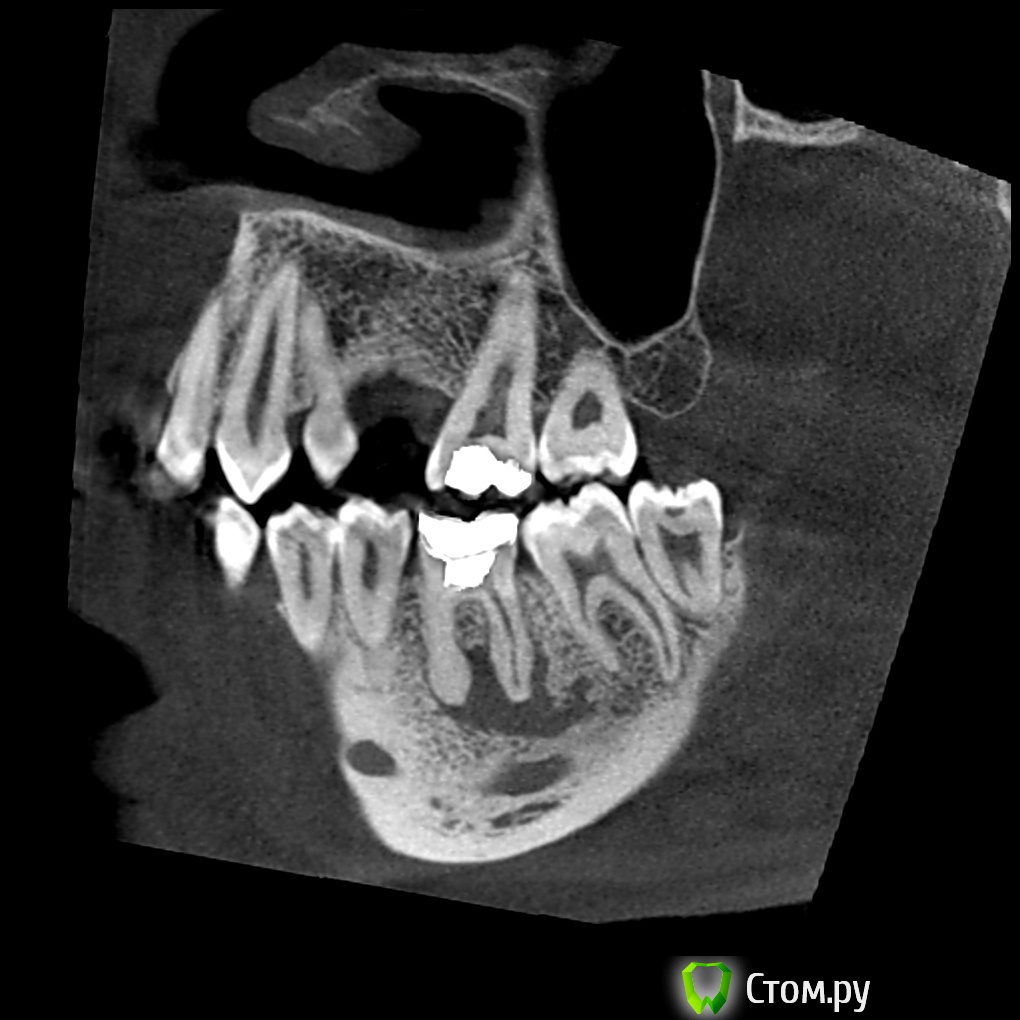

turlih) Опубликовано 29 декабря, 2013 Поделиться Опубликовано 29 декабря, 2013 (изменено) Добрый вечер.От коллеги сегодня пришла ссылка на любопытное КТ, с целью консультации. Пациент, 30 лет, жалобы на неприятные ощущения при накусывании. Зуб 36 впервые был лечён в возрасте 12лет, последний раз лечили 3 года назад. Тогда неизвестный доктор сказал, что каналы запломбированы, всё ок и нужно только заменить пломбу. Что и было сделано.Теперь собственно план лечения:Эндодонтическое лечение 3.6, 3.7, кистэктомия, РВК 3.6. и медиального корня 3.7 с ретроградным пломбированием.Ситуация осложнена тем, что 12 числа пациент уезжает из страны на 3 - 6 месяца минимум. Док боится обострения. Варианты эндолечения 3.6 без РВК или удаления с последующей имплантацией были отвержены коллегой как несостоятельные, ибо киста останется, будет расти.Также отдельное эндолечение 3.6 и отсутвие возможности наблюдать пациента вызывает опасение. Хирургический этап (в связи с грядущими праздниками) возможно произвести только за 4 дня до отъезда.Ваши мысли по этому поводу? Спасибо. Изменено 29 декабря, 2013 пользователем turlih) Ссылка на комментарий

turlih) Опубликовано 29 декабря, 2013 Автор Поделиться Опубликовано 29 декабря, 2013 В 37 оператора смутила эта картина: И ретроградное пломбирование тоже рассматривают как вариант, но без УЗ насадок, микрозеркал и увеличения. В 3.7 выводить массу за апекс не собирались, эндо с резекцией верхушки медиального корня 3.7 Ссылка на комментарий

Yurij.k Опубликовано 29 декабря, 2013 Поделиться Опубликовано 29 декабря, 2013 В 37 оператора смутила эта картина:11.jpg И ретроградное пломбирование тоже рассматривают как вариант, но без УЗ насадок, микрозеркал и увеличения. В 3.7 выводить массу за апекс не собирались, эндо с резекцией верхушки медиального корня 3.7 Резекция без ретроградного пломбирования - напрасно истраченное время.Зачем 3.7 калечить ? Здесь без хирургии можно обойтись! Нужно качественное эндо. Лечение 3.6. 1 Ссылка на комментарий